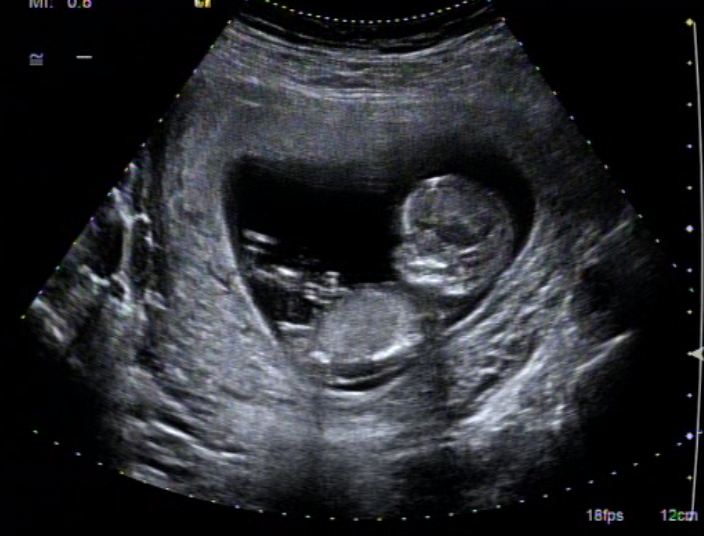

I absolutely love the nub gender theory, it's so fascinating to me. I had my NT scan yesterday at 12+3 but the baby measured 13 weeks actually. I also see a pretty clear fork but I'm not sure if that means anything. I have different kinds of nub shots so I am also adding a link to a youtube video (I recommend starting at 7 minutes). Thank you so much!

Attachment 9186

Attachment 9187

Attachment 9188

Attachment 9189